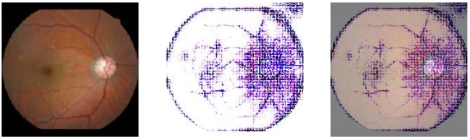

서울대병원은 박상민 교수팀이 건강증진센터에서 12년간 축적된 빅데이터를 활용해 15,408개의 안저사진을 기반으로 죽상동맥경화를 찾아내는 인공지능 모형을 개발했다고 10일 밝혔다.

박상민 교수(가정의학과)는 “눈은 혈관 건강을 직접 볼 수 있는 유일한 장기”라며 “기존에는 경동맥 초음파를 통해서만 알 수 있는 경동맥경화를 연구팀이 개발한 인공지능 진단법를 통해 안저영상으로 정확하게 평가할 수 있게 됐다”고 강조했다.

장주영 연구원(1저자)은 “인공지능 안저 동맥경화 진단법은 망막 혈관 등의 해부학적 요소를 이용하여 동맥경화를 예측한다”며 “기존 인공지능 연구는 안저사진 촬영 시점만을 분석하여 임상적인 의미가 크지 않았으나 후향적 코호트를 구성해 추후 발생하는 심혈관 사망을 예측했다는 점에서 임상적 의미를 찾을 수 있다”고 설명했다.